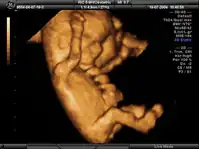

La ecografía obstétrica[1] es un procedimiento médico usado para determinar la presencia de embarazo y conocer las condiciones del embrión o feto, así como de la placenta, útero, cuello del útero y líquido amniótico. La ecografía es un procedimiento de diagnóstico que emplea el ultrasonido compuesto para crear imágenes bidimensionales o tridimensionales. Un pequeño instrumento (muy similar a un micrófono) llamado transductor emite ondas de ultrasonidos. Estas ondas sonoras de alta frecuencia se transmiten hacia el área del cuerpo bajo estudio y se recibe su eco, el cual es procesado por una computadora que muestra una imagen de los órganos o el feto sobre los que ha incidido el ultrasonido.

Esta técnica se considera el método más seguro para conocer el estado general del embarazo y, según las semanas de gestación, tiene sus indicaciones específicas. El examen se lleva a cabo a través de imágenes. Las ondas sonoras reflejadas en el interior del vientre materno permiten ver el desarrollo del feto dentro del útero de la madre. También se usa para ver los órganos pélvicos de la madre durante el embarazo. La ecografía obstétrica no emplea radiación ionizante.

Antes de realizar la ecografía, se recomienda que la madre beba 2 o 3 vasos de agua 1 hora antes de la prueba, para llenar la vejiga y así obtener una mejor imagen. La madre permanecerá acostada durante el procedimiento, mientras el ecografista aplicará un gel a base de agua en el abdomen, vientre y pubis. Este gel permitirá que las ondas sonoras enviadas por la sonda manual sean transmitidas al interior del abdomen materno. Estas ondas rebotarán sobre el feto o embrión, para producir una imagen en el ecógrafo. La imagen obtenida permitirá evaluar el estado de la gestación y el desarrollo del embrión o feto.